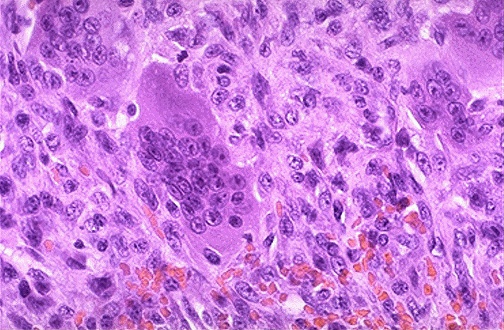

Histologically, giant cell tumors of bone as seen here are composed of osteoclast-like multinucleated giant cells in a sea of round to oval mononuclear stromal cells. There may also be foamy macrophages and hemosiderin deposition in the stroma. Though these tumors are biologically benign, they can expand and cause pain, deformity, or fracture. They are treated by curettage or resection, but when radiated, they may undergo malignant transformation.